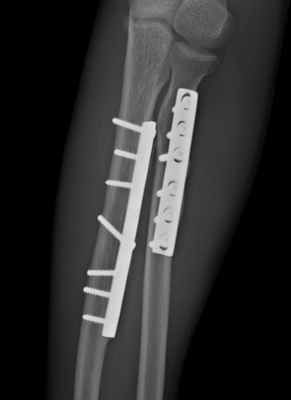

Остеосинтез лучевой/локтевой кости пластиной

После выставления отломков в правильное положение металлическая пластина фиксируется на кости с помощью специальных винтов, не давая отломкам сместиться. Если сломаны и лучевая, и локтевая кость, устанавливается две пластины. После операции на руку накладывается защитная гипсовая лонгета, в среднем – на 2-3 недели. Средний срок госпитализации при подобном оперативном вмешательстве – 7 дней. После выписки необходимо делать перевязки в амбулаторном режиме (в поликлинике). Через 2-3 недели лонгета снимается, и назначается курс восстановительного лечения – лечебная физкультура, физиотерапия. Пластины удаляются в среднем через год.

В ходе этой операции устраняют смещение отломков и скрепляют кость металлической конструкцией, выбор которой определяется характером перелома.

Операционный доступ: 1. Доступ Томсона; 2. Доступ Генри; 3. Доступ к локтевой кости.

Положение пациента на спине. Обезболивание: проводниковая анестезия или эндотрахеальный наркоз. Операция выполняется в кратчайшие сроки с использованием современных методик и имплантов. Импланты производства Швейцария и Германия. Материал имплантов: титан или медицинская сталь.